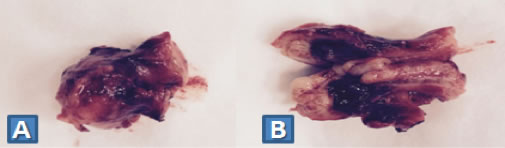

Α. Βλεννώδες κυσταδένωμα (καλοήθης βλεννοκήλη) ως τυχαίο ιστολογικό εύρημα σε παρασκεύασμα σκωληκοειδεκτομής.

Β. Επιμήκως διανοιγμένο παρασκεύασμα

(Από το προσωπικό αρχείο του Γ. Θεοδωρόπουλου)